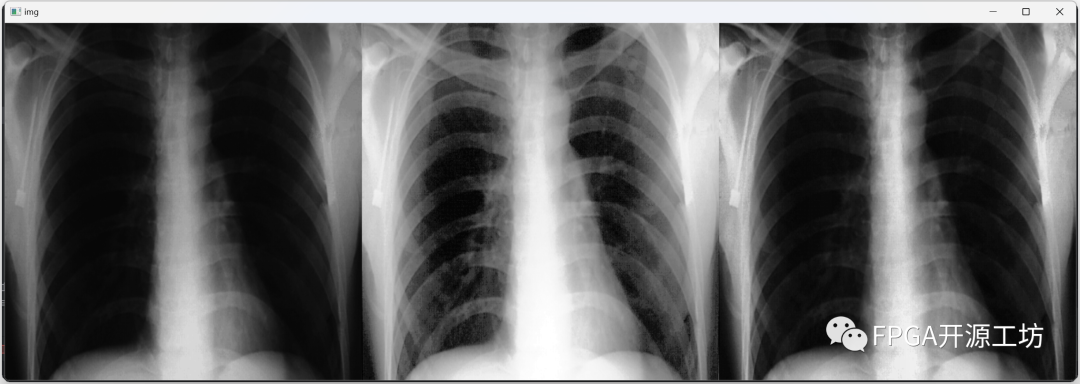

如下图就是经过直方图均衡化后的效果图。

ee96a1f8-a923-11ee-8b88-92fbcf53809c.png

左边是原图,右边是经过直方图均衡化后图,可以看到肋骨什么的可以更加清晰的显示了出来,能够更好的观察到肋骨等位置的细节。

但是美中不足的是总感觉有的地方太亮了,干扰到了我们的观察。